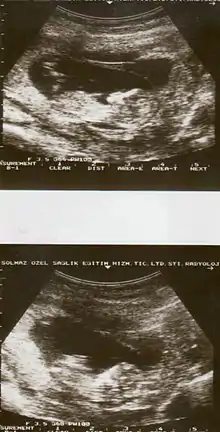

![]() | |

| Drawing of internal and external bleeding from placental abruption | |